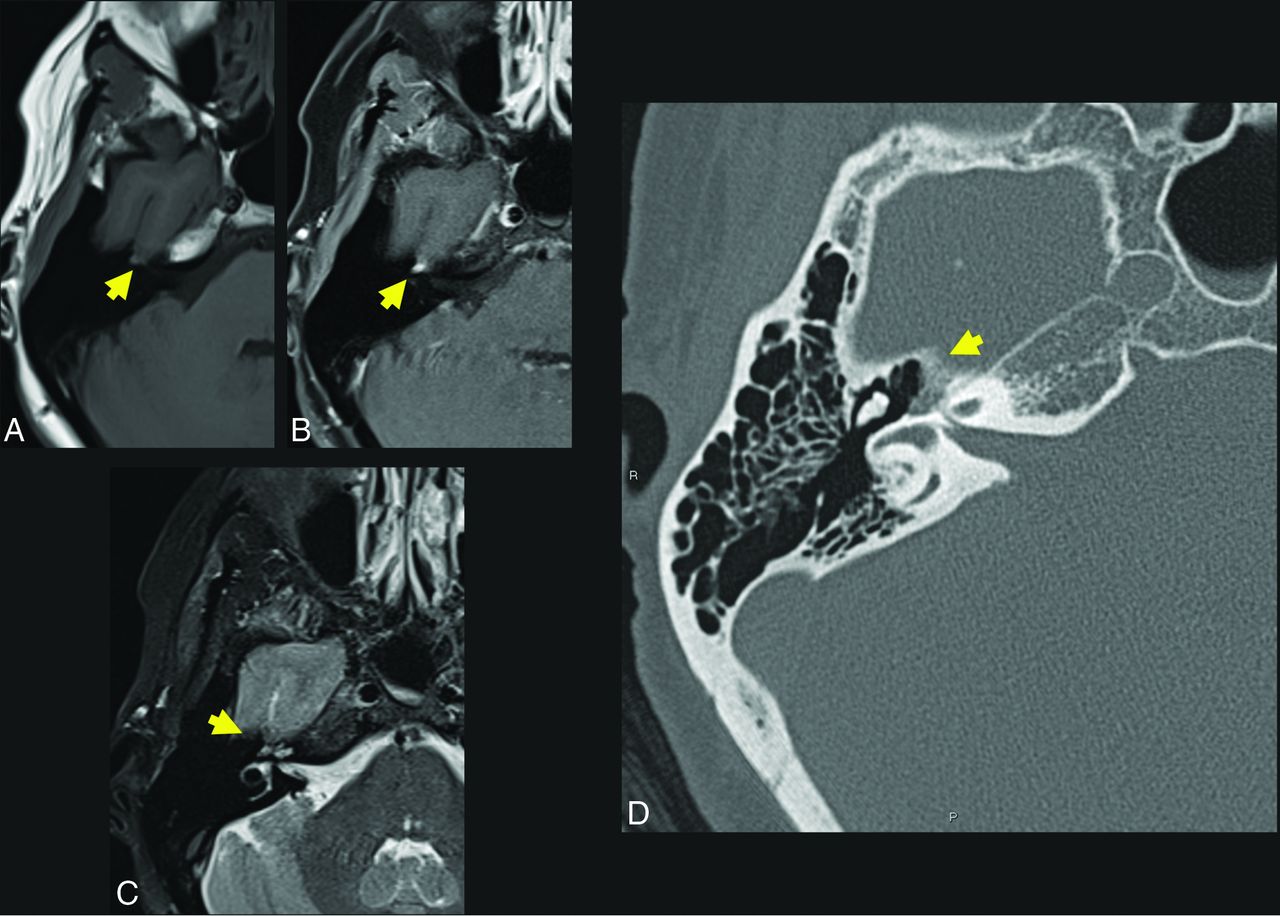

A 57-year-old woman who presented with right facial synkinesis. Noncontrast T1WI (A) and contrast-enhanced T1WI (B) demonstrate an enhancing lesion centered at the level of the right FN hiatus (yellow arrow, A and B), with corresponding increased signal on T2WI (C, yellow arrow indicates lesion). Differential considerations included both schwannoma and IOVM of the FN. Axial (D) thin-section CT of the temporal bone demonstrates an expansile, lucent lesion at the level of the anterior genu of the FN and FN hiatus (yellow arrow, D). The internal trabeculae help to confirm the diagnosis of IOVM because schwannoma would be less likely to show internal calcification. The diagnosis of IOVM was confirmed on pathology.

The location for an IOVM is characteristically at the geniculate portion of the FN, which is not surprising given its rich venous and capillary plexus. There is a rarer occurrence elsewhere along the FN, namely at the internal auditory canal or second genu.39 FN IOVMs often infiltrate beyond the margins of the FN canal and geniculate ganglion, aiding in discrimination from facial nerve schwannoma.

CT typically reveals an expansile lesion with irregular margins centered at the geniculate fossa, demonstrating characteristic internal bony spicules or trabeculae, a honeycomb pattern, or small, needle-shaped calcifications as recently described by Yue et al.40 However, when small, an FN IOVM may fail to show typical bony densities and only widen the FN canal. Discrimination may then prove difficult between an IOVM and neoplasm, most commonly a schwannoma in this location.41 MR imaging typically reveals a mass of T1-hypointense or -isointense and T2-hyperintense signal that may be heterogeneous depending on degree of bony matrix. Typically, an FN IOVM appears as a patchy or geographic focus of enhancement, whereas a schwannoma may appear ovoid or tubular. Particularly when lesions are small, differentiation may be very difficult, and ultimately both CT and MR imaging are frequently required in this differential diagnosis.